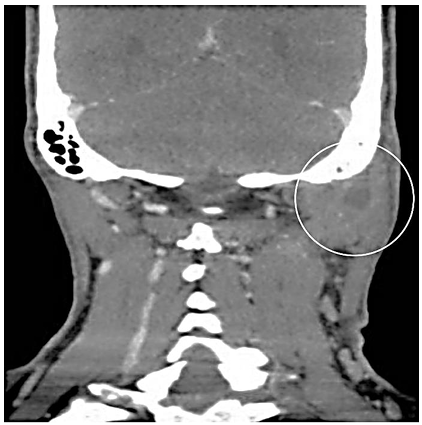

Homem, 46 anos, com quadro de otorreia, otalgia, febre e edema cervical ipsilateral às queixas otológicas, é submetido à tomografia computadorizada de mastoides com contraste (imagem abaixo):

Enunciado 4713918-1

Acerca do caso em questão, o diagnóstico mais provável e a conduta mais adequada é: